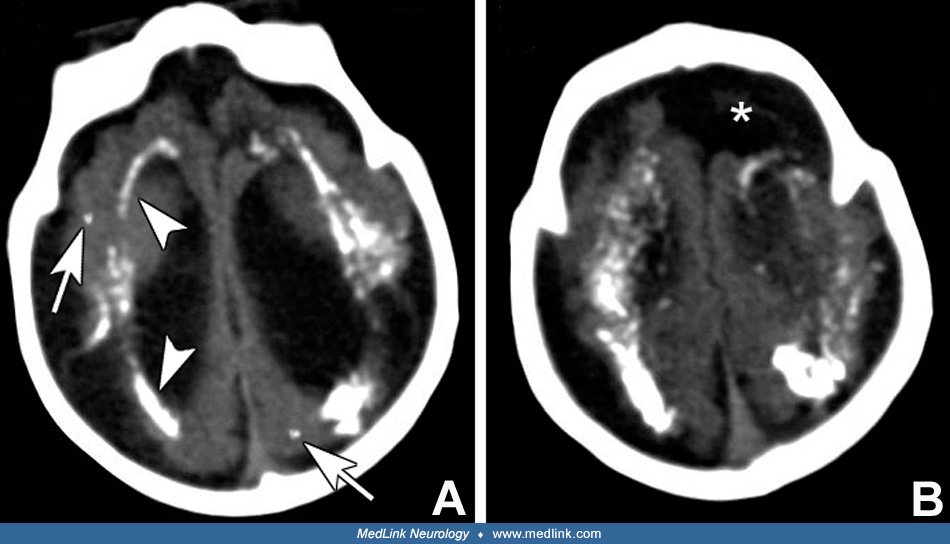

Babygirl with hydrocephalus due to congenital toxoplasmosis. (Dubey Has Anyone Had A Baby Born With Toxoplasmosis Most babies with toxoplasmosis seem healthy at birth. Hey all, i am 15 weeks pregnant and tested positive for toxoplasmosis. A fetus may be born prematurely, and a newborn may have problems such as a small head or an enlarged liver. How did you know you had it, did or does baby have any defects, and could they tell from. Has Anyone Had A Baby Born With Toxoplasmosis.